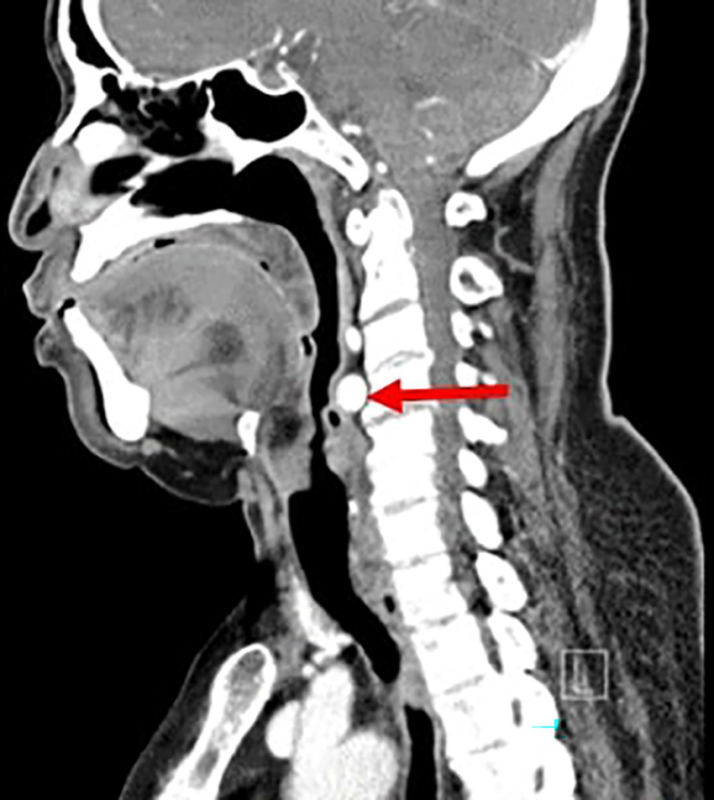

۵. CT Scan (سی تی اسکن) حلق و حنجره

روش انجام

از اشعه ایکس و رایانه برای ایجاد تصاویر مقطعی سه بعدی استفاده می شود.

کاربردها

- تشخیص تومورها و گسترش آنها

- بررسی شکستگی های غضروف حنجره

- بررسی توده های گردن

- ارزیابی قبل از جراحی تومور

- تشخیص انسداد راه هوایی